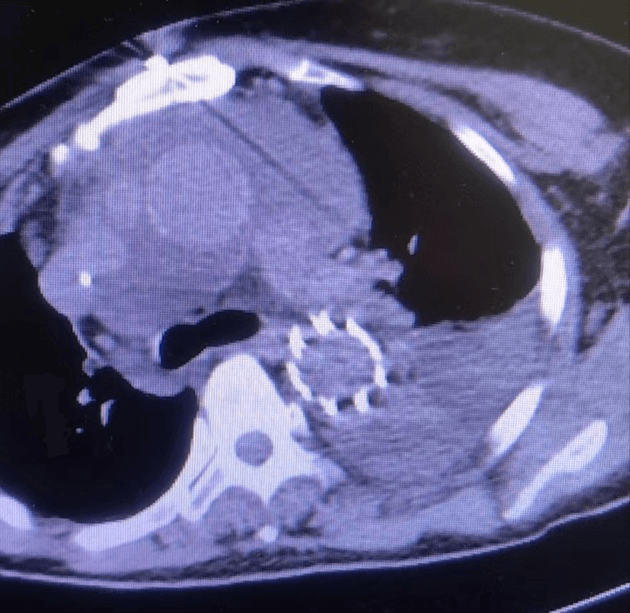

近日,我院急診科會(huì)診來(lái)了一位60歲女性患者,患者訴胸背部疼痛4小時(shí)余,疼痛劇烈,不能忍受,來(lái)院時(shí)血壓260/135mmHg,于當(dāng)?shù)乜h醫(yī)院行大血管CTA檢查,提示主動(dòng)脈夾層。新型冠狀病毒感染未完全康復(fù)的值班醫(yī)生一路小跑都?xì)獯跤跚巴痹\科會(huì)診,一邊咳嗽一邊問(wèn)診,由于患者病情危急,請(qǐng)示心外科武小剛科主任后分析:患者系主動(dòng)脈夾層動(dòng)脈瘤(A型),降主動(dòng)脈近段可見(jiàn)明顯破口,升主動(dòng)脈明顯增寬,根據(jù)超聲提示,目前考慮升主動(dòng)脈已有新的破口,需急診行外科手術(shù)治療。與家屬溝通后積極降壓、止痛、備血等,進(jìn)入夾層綠色通道,經(jīng)過(guò)快速的術(shù)前準(zhǔn)備,患者及早進(jìn)入手術(shù)室,術(shù)中仔細(xì)剝離血管及周圍組織,小心翼翼的分離出受累血管,嚴(yán)格控制血壓,避免因血壓過(guò)高導(dǎo)致血管破裂,建立體外循環(huán)術(shù)中探查升主動(dòng)脈可見(jiàn)1cm破口,驗(yàn)證了術(shù)前的判斷;剪除掉破損血管,植入人工血管,仔細(xì)吻合每一根血管,既不能讓吻合口過(guò)小導(dǎo)致血液供應(yīng)不足,也不能讓吻合口出血,一臺(tái)“升主動(dòng)脈置換+全弓置換+象鼻術(shù)”需要經(jīng)過(guò)長(zhǎng)達(dá)6~8小時(shí)高精度操作,對(duì)醫(yī)生的耐力和精神都是一種考驗(yàn),經(jīng)過(guò)6小時(shí)的手術(shù),順利拆除“炸彈”。主刀醫(yī)師從手術(shù)室出來(lái),已經(jīng)是凌晨2點(diǎn)鐘,脫掉早已被汗水浸透的手術(shù)衣,癱軟的坐在椅子上,但患者轉(zhuǎn)危為安,再大的疲憊都是值得的。

術(shù)后復(fù)查恢復(fù)良好